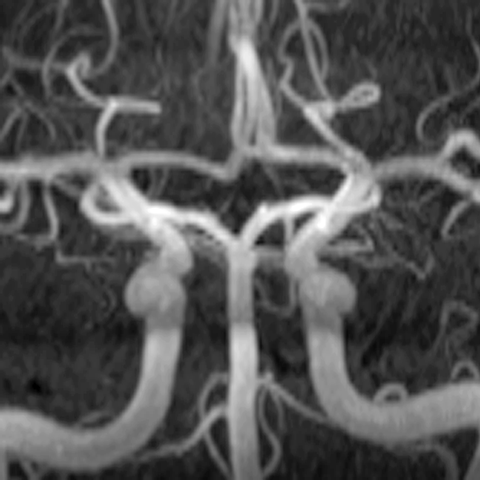

Circle of Willis (MRA) [4 of 6]